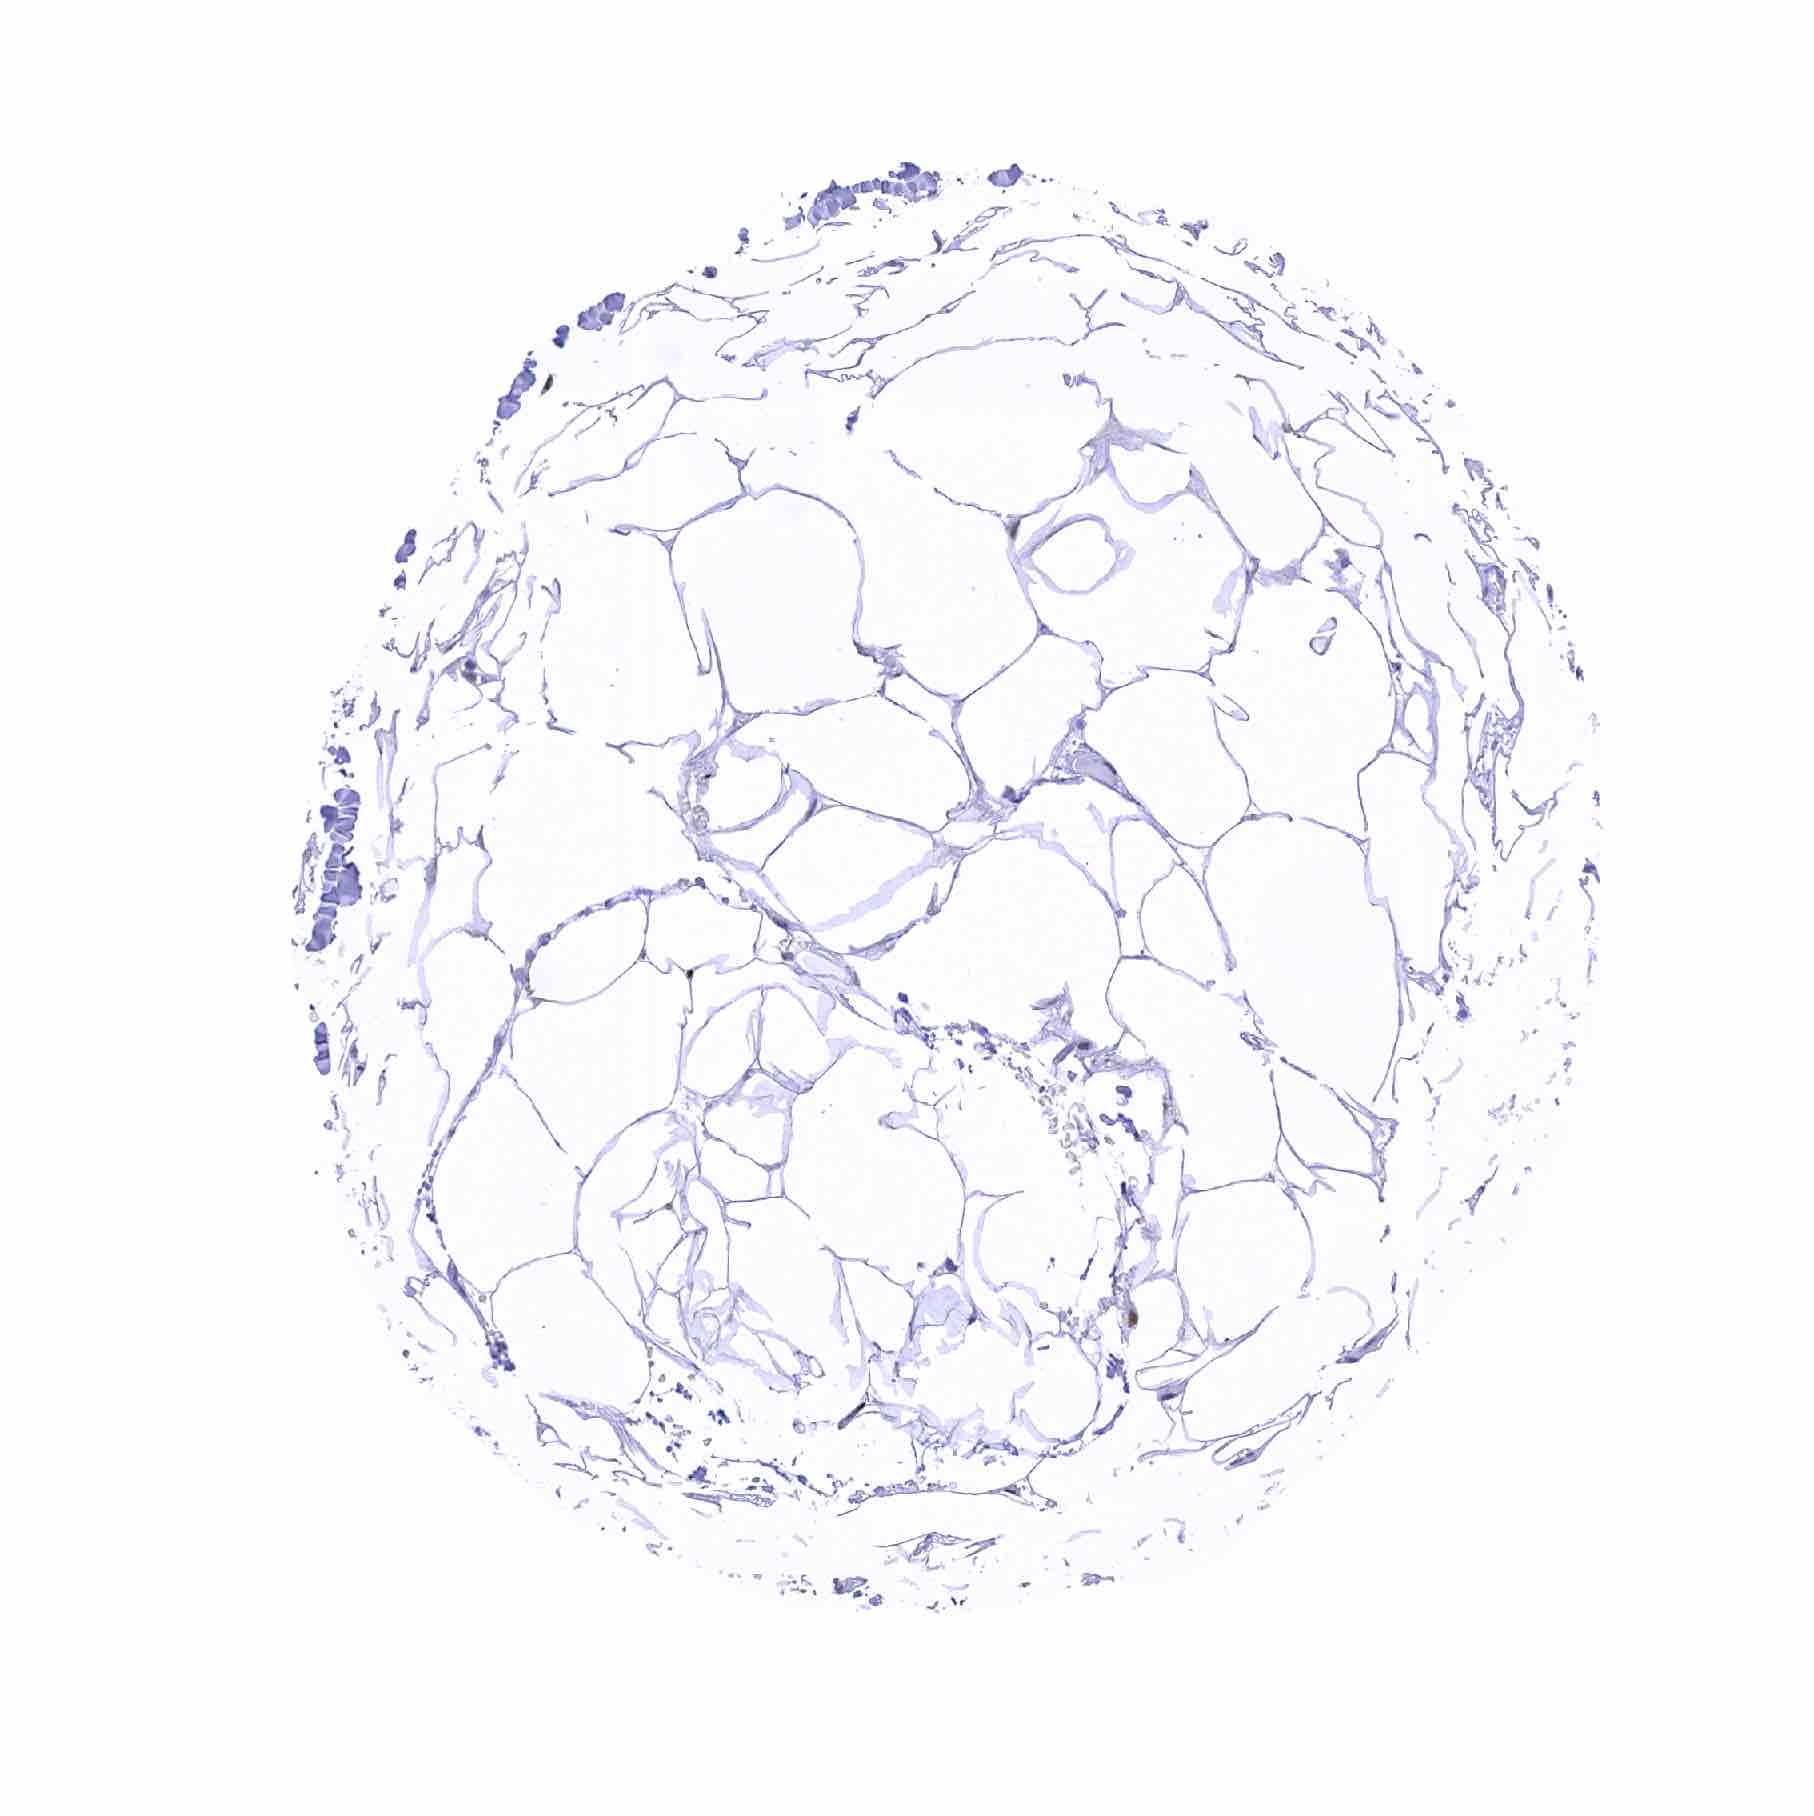

Normal Tissue Gallery- GTX640556

53BP1 antibody [HMV324] HistoMAXTM

Fat